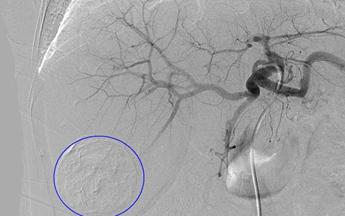

Nút mạch hóa chất (TACE- Transarterial Chemoembolization) là kĩ thuật đưa hoá chất điều trị và vật liệu gây tắc mạch vào khối u qua đường động mạch gan, khiến u hoại tử do thiếu nguồn cấp máu, đồng thời giúp hoá chất điều trị được giữ lại trong khối u lâu hơn. TACE là phương pháp điều trị phổ biến nhất và là điều trị tiêu chuẩn cho nhóm bệnh nhân HCC giai đoạn trung gian

Hình 1: Hình ảnh khối u gan sau can thiệp nút mạch hóa chất (TACE)